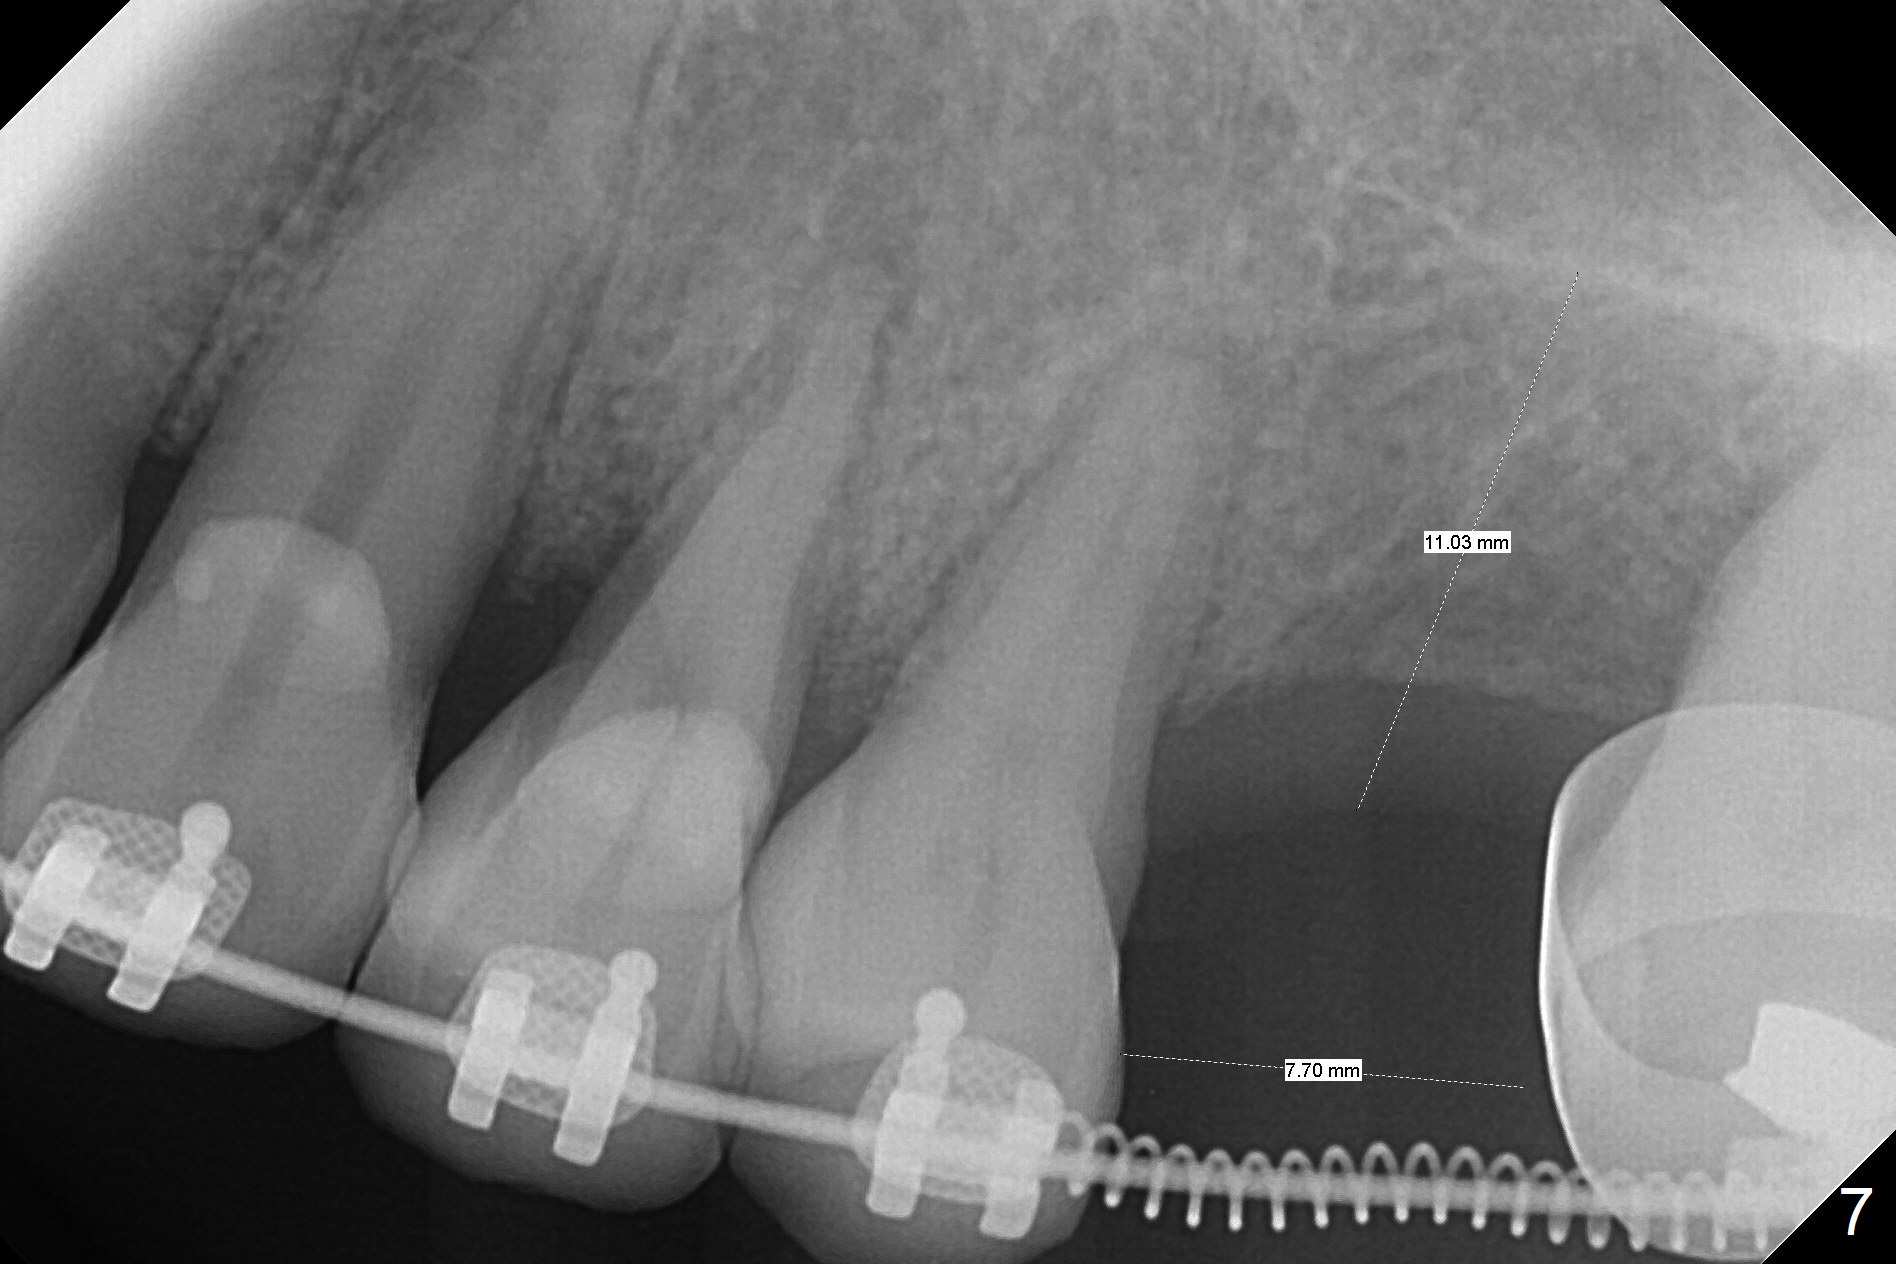

A 54-year-old woman had #14 extracted in China 1 year ago (Fig.1,5). The tooth #15 has undergone mesial shift and tilt (Fig.2,4, as compared to Fig.3). The edentulous space is too narrow for implant placement (Fig.6). It appears that traditional orthodontic appliance should be placed from UR6 to UL7 in addition to a mini-implant distal to UL7. Take Alginate impression before treatment. Since the implant at UR7 is placed apparently too deep, a band will be placed when it is initially osteointegrated (6-8 weeks postop). Fabricate a well-fit provisional with permanent cementation before banding. In fact, brackets and bands are placed between UR3 and UL7. In 6 months, the meisodistal space at #14 is enough to place an implant (Fig.7).